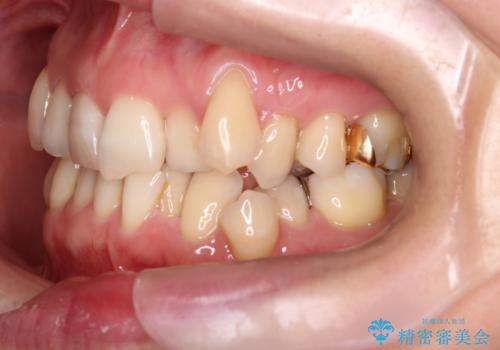

- 40代女性

- 2年4ヶ月

- 上下の歯の凸凹を主訴に来院されました。

他院では抜歯+ワイヤー矯正の提案をされているとのことでした。

当院での検査にて非抜歯+インビザライン矯正を提案させていただき治療を行なっております。